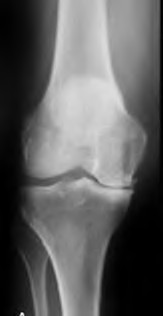

Question 13:

A 32-year-old woman complains of left knee pain. Radiographs show an eccentric, purely lytic lesion in the distal femoral epiphysis extending to the subchondral bone, without a sclerotic margin. Biopsy reveals multinucleated giant cells interspersed among mononuclear stromal cells. For recurrent or surgically unsalvageable cases of this specific tumor, which of the following is the most appropriate targeted medical therapy?

Correct Answer: Denosumab

Explanation:

This is a Giant Cell Tumor (GCT) of bone. The neoplastic cells in GCT are actually the mononuclear stromal cells, which heavily express RANKL (Receptor Activator of Nuclear factor Kappa-B Ligand). This expression recruits and activates normal osteoclasts (the giant cells), causing massive osteolysis. Denosumab, a monoclonal antibody against RANKL, is the medical treatment of choice for unresectable or highly recurrent GCTs.